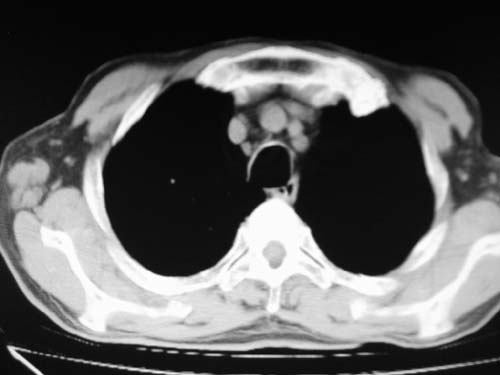

肺动脉段突出,左右肺门不等大,左肺门明显增大,肺动脉干及左肺动脉明显增宽,考虑先天性肺动脉狭窄瓣膜狭窄型。

左肺动脉异常增粗,考虑肺动脉狭窄可能。

左肺动脉异常增粗,建议增强。

肺动脉高压,左肺动脉瘤样扩张。

1)考虑左肺动脉瘤可能性大,建议增强。2)右肺上叶继发性肺结核。3)右侧胸膜增厚、钙化,左侧胸膜反应。